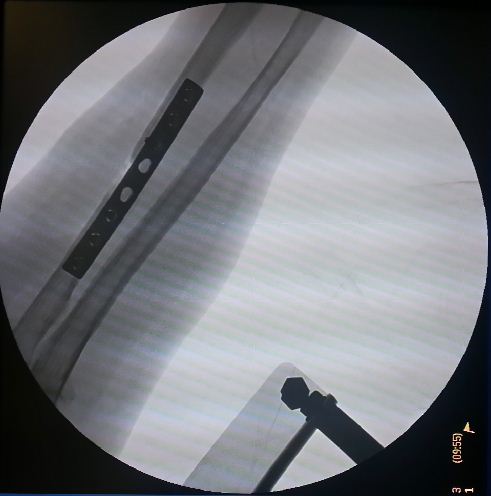

Η ελάχιστα επεμβατική οστεοσύνθεση (Minimal Invasive Plate Osteosynthesis) αποτελεί εξέλιξη της εσωτερικής οστεοσύνθεσης και περιλαμβάνει τη συγκράτηση ενός κατάγματος σε ανάταξη με τη χρήση ειδικών εμφυτευμάτων. Ο σχεδιασμός των εμφυτευμάτων αυτών δίνει τη δυνατότητα στο χειρουργό να τα τοποθετήσει μέσω μικρών δερματιών τομών χωρίς να ανοίξει την καταγματική εστία.